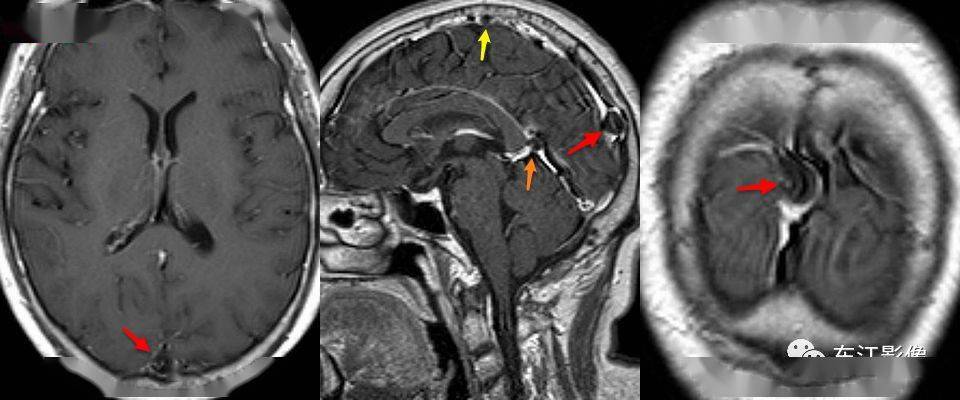

患者初诊时头颅磁共振.上海新华医院 供图

莫名头晕头痛竟因脑中长虫这个食物一定要煮熟